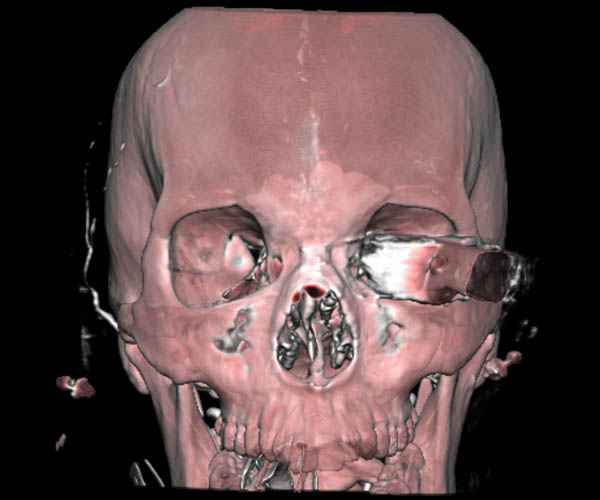

В своих выступлениях я рассказывал, что наши центры в мирное время по пенетрирующим травмам не уступает Ираку или Афганстану, и вот недавно к нам поступила больная 22 лет, травма "ножом в глаз" от бывшей подруги нынешнего "бой френда".

При поступлении в сознании, жаловалась на неприятные ощущения в глазнице.

По протоколу сделаны все необходимые исследования: рентген, ангиограмма с 3Д реконструкцией, где обнаружили что все жизненно важные сосуды не задеты, даже некоторые "сидят" изгибаясь на ноже.

Одним махом нож удалить не удалось, пришлось раскачать и потом двумя руками удалили нож. Рана без кровотечения, обработана и зашита.